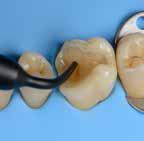

Biodentinee in Bio-Bulk

Fill Procedure

as

How long have you been using Biodentinee™ ?

I switched from MTA to Biodentinee™ five years ago.

Why do you use the Bio-Bulk Fill procedure with Biodentinee™ ? What are the main advantages for you? Firstly, if I have sufficient time at the appointment I can wait for the Biodentinee™ to fully set (12 minutes) and then complete the permanent restoration without fear of damaging the Biodentinee™. Secondly, in what is usually the case, if I have insufficient time to wait for the set and then complete the restoration, I can simply fill the cavity completely with Biodentinee™, wait for the complete set (12 minutes), discharge the patient, and then reappoint them at a later date to cut back the Biodentinee™ and cover it with the final restoration. I often use this latter technique to allow time to assess Biodentinee™’s effect on the pulp tissue, whether it be a pulpotomy, deep cavity or symptomatic crack, before committing to the final restoration, especially if an indirect restoration is planned.

Summary

Teeth with cracks that exhibit symptoms of moderate to severe pulpitis have historically been treated by pulpectomy, root canal treatment and then restoration with full-coverage indirect restoration. With the success of pulpotomies using calcium silicate cements, many of these teeth have been able to retain their vitality and arguably increase their longevity.

Methods

A full pulpotomy was performed on tooth 26 using Biodentinee™ with the Bio-Bulk Fill technique, with a permanent dentine restoration and interim enamel restoration to allow time to assess the success of the vital pulp therapy. The Biodentinee™ then acted as a core for the indirect restoration.

Discussion

Numerous studies have demonstrated that the success rate of partial and full pulpotomies ranges from 75-100%.(2,3) It has been advocated as the preferred option for treating teeth with symptoms once described as irreversible pulpitis.(4,5) While there is little published data on the use of pulpotomy in cracked teeth, my own professional experience has shown this

to be a viable treatment option for these symptomatic teeth

Conclusion

Full pulpotomy and restoration with an indirect full- coverage restoration is a viable treatment option for cracked teeth with symptoms of moderate to severe pulpitis.

Introduction

Symptomatic teeth that are found to have cracks are one of the more difficult situations for which to plan treatment. Many articles have been published regarding these teeth and unfortunately, there has been no consensus on the best course of treatment. In my experience, it is best to treat these teeth conservatively as this allows for further treatment options if the conservative treatment fails.

Case report by Dr. M. Paul Renner

Clinical signs and symptoms

In 2018, a 59-year-old patient presented with vague pain in the upper left region. He had difficulty locating which tooth was painful, but he reported that he thought it was one of the last two teeth (tooth 26 or 27).

No teeth were tender to percussion. Tooth 26 reacted strongly to cold testing while the other teeth reacted normally. Tooth 26 tested positive to biting on damp gauze but the sensation did not linger. Both tooth 27 and 25 were negative to the bite test. The composite resin restoration in tooth 26 was removed under rubber dam and crack lines could be seen under the restoration (Fig. 1), with the most obvious running from the lingual to the centre of the tooth, and another from the mesiobuccal to the centre. A number of other minor cracks were visible, including one that ran under the buccal cusps (Fig. 1).

a core material for indirect restoration

Fig. 1

These crack lines were discussed with the patient and he was given the option of either restoring the tooth with direct composite resin or with a full- coverage indirect restoration. The patient chose to have the tooth restored with a direct composite resin and so this was performed at this appointment. The patient returned annually for examination and reported the tooth was asymptomatic.

In 2024, the patient presented again with pain in tooth 26. He reported the tooth was very sensitive to cold, with the pain lasting several minutes. He also reported that the tooth had ached spontaneously at times. On examination, the tooth reacted very strongly to cold, which lasted for almost one minute. The tooth was also slightly tender to percussion. The composite resin restoration appeared sound (Fig. 2). A PA radiograph (Fig. 3) revealed no PARL, but the pulp chamber was reduced in size when compared to a previous bite-wing radiograph.

Diagnosis

Given the tooth’s previous history of visible cracks running into the tooth and the current symptoms of moderate to severe pulpitis, a decision was made after discussion with the patient to enter the pulp chamber to assess the condition of the pulp and the depth of the cracks. The plan was to either perform a full pulpotomy or, if no viable pulp tissue was present, extirpate the pulp.

Procedure and treatment

Using local anaesthetic and rubber dam isolation, access was obtained through the composite resin restoration. While the cracks were visible, they appeared similar to the image from 2018 (Fig. 4). The roof of the pulp chamber was removed and vital tissue was found, which did not appear to be heavily inflamed (Fig. 5). A pulp stone was also present (Fig. 6). Removing this revealed bleeding pulp tissue at the opening of the root canals. A cotton pellet soaked in NaOCl was placed on the pulp tissue at the opening of the root canal and after five minutes the bleeding had ceased (Figs. 7 and 8).

As the plan was to restore the tooth with a full- coverage indirect restoration, the entire pulp cavity was filled with Biodentinee™ with the Bio-Bulk Fill technique. (Fig. 9).

The patient returned after twelve weeks and reported that the tooth had been asymptomatic (Fig. 10). At this appointment, a preparation for a ¾ crown was performed (Fig. 11). The Biodentinee™ was left in situ, cut back and used as a core for the restoration. A PVS impression was recorded, and a BISAcrylic temporary crown cemented with provisional cement (Fig. 12).

Three weeks later, a monolithic zirconia crown (Fig. 13) was bonded onto the tooth (Fig. 14). The tooth will be monitored and a review radiograph taken after six months.

Fig. 2: Pre-op composite resin restoration, 2024.

Fig. 5: Initial exposure of the pulp chamber showing slight bleeding and pulp stone.

Fig. 3: PA radiograph.

Fig. 6: Pulp stone removed.

Fig. 8: Palatal root opening with vital tissue after bleeding has stopped.

Fig. 4: Initial access showing existing cracks.

Fig. 10: Tooth at 12-week review.

Fig. 7: Buccal root openings with vital tissue after bleeding has stopped.

Fig. 9: Cavity filled with Biodentinee™.

This case highlights a number of elements of pulpotomies in teeth with cracks. Firstly, many teeth with deep cracks have a long-standing mild pulpitis, to which the pulp has responded by producing reparative dentinee that often appears in the form of a pulp calcification. The operator must be careful when performing vital pulp therapy on these teeth as it is often difficult to differentiate the pulp calcification from the floor of the pulp chamber.

Any pulp calcifications must be removed before assessing the condition of the radicular pulp tissue.

Secondly, in teeth with pulp symptoms resulting from cracks, it is best to perform a coronal pulpotomy. This allows the floor of the pulp chamber to be examined for any extension of the crack across the floor, which would greatly reduce the prognosis for the tooth.

The ability to use Biodentinee™ in the Bio-Bulk Fill technique has a number of advantages in cases like the above.

The initial vital pulp therapy appointment can be shortened by completely filling the cavity and using the Biodentinee™ as a permanent dentine replacement and an interim enamel replacement. The fact that the material can be left for up to six months allows time to assess the success of the procedure before committing to the final indirect restoration. The strength of Biodentinee™ means there is no requirement to place a separate core material.